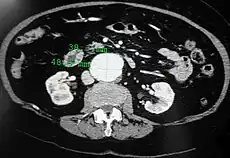

An axial contrast-enhanced CT scan demonstrating an abdominal aortic aneurysm of 4.8 by 3.8 cm